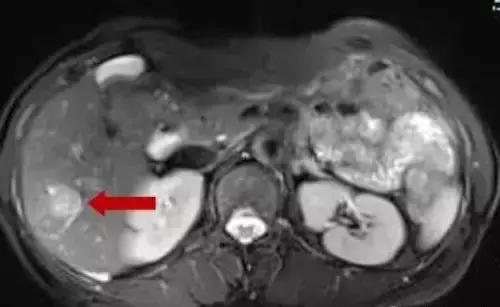

患者,女性,60岁,因反复右下腹疼痛3月,阵发性,可自行缓解,无呕吐,无发热,无胸闷、心悸,大便每日一次,无便血,无血尿,今我院肠镜检查提示:升结肠占位。门诊以“升结肠肿瘤”收治入院进一步诊治。入院后实验室检查:CEA:23.23ng/ml,行CE-MR和PET-CT均提示伴肝右叶后下段转移,大小约2cm。

肝右后叶转移灶